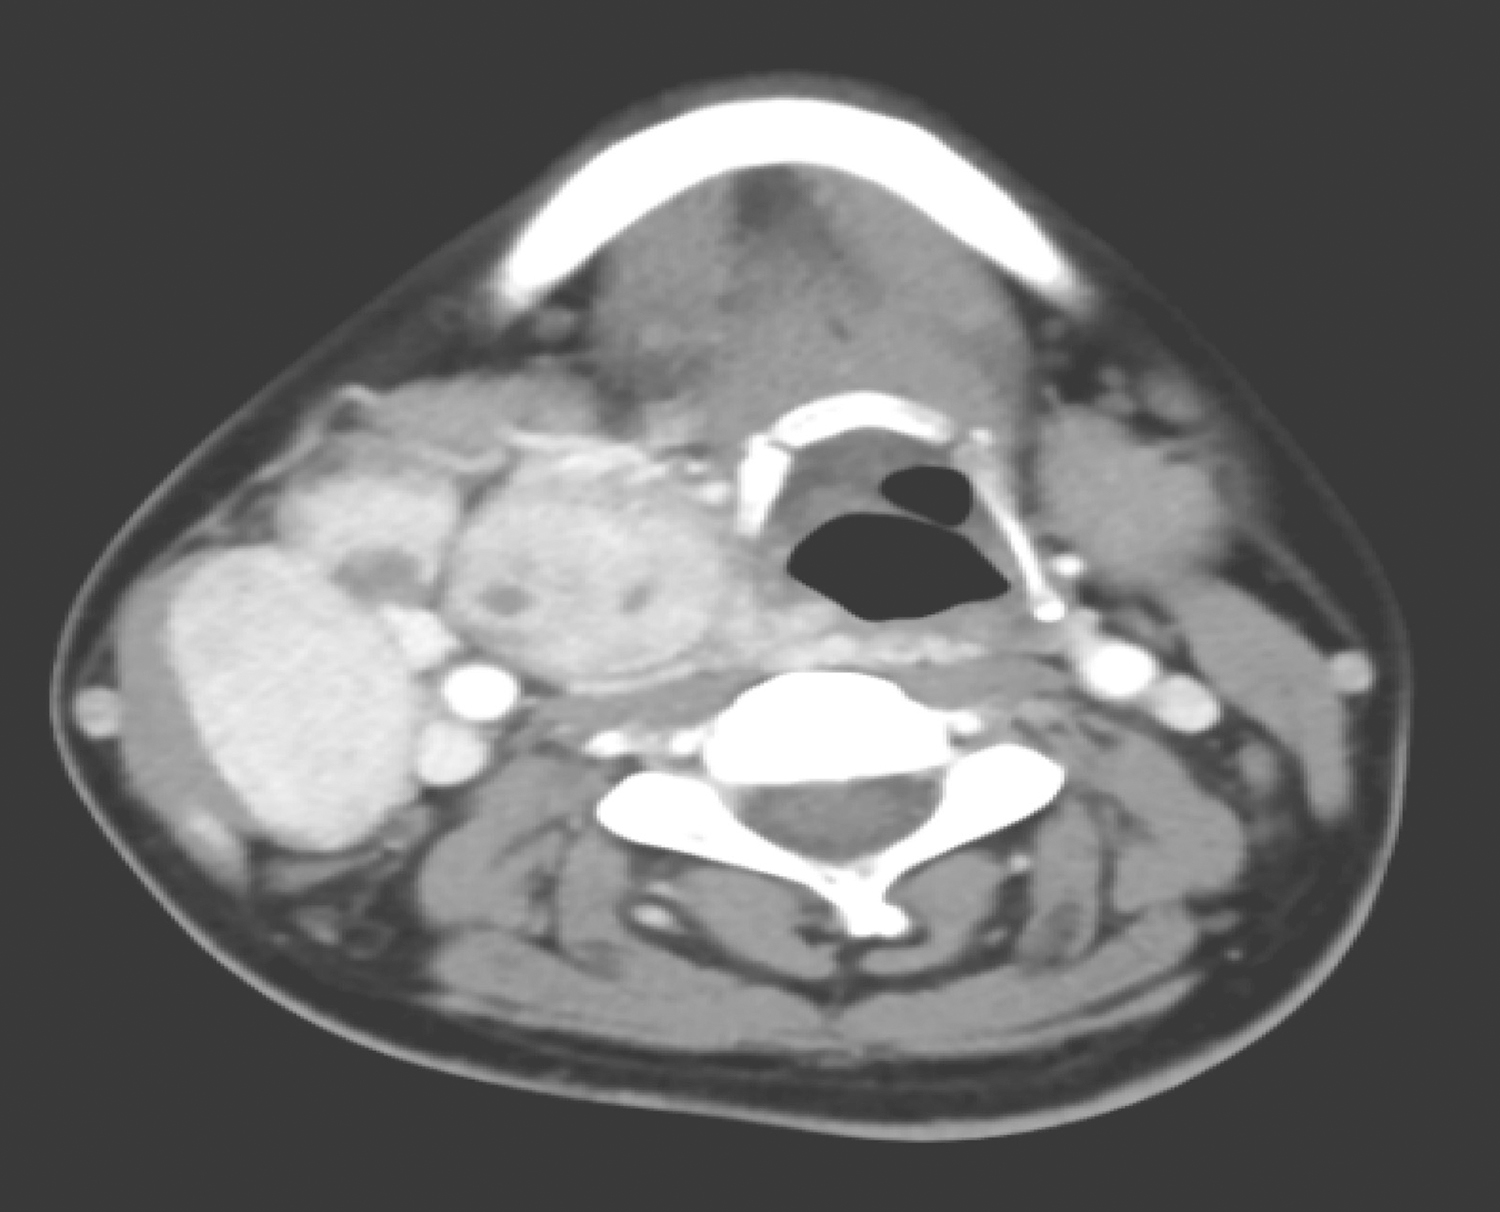

1小时条评论在伊马替尼问世之前,复发转移的巨大胃肠间质瘤(gastrointestinal stromal tumor,GIST)患者的生存质量和生存率都较低,外科手术切除风险较大,较难达到R0切除,患者术后预后不佳。伊马替尼的出现在一定程度上改变了这一现状,目前越来越多的学者认为,伊马替尼术...